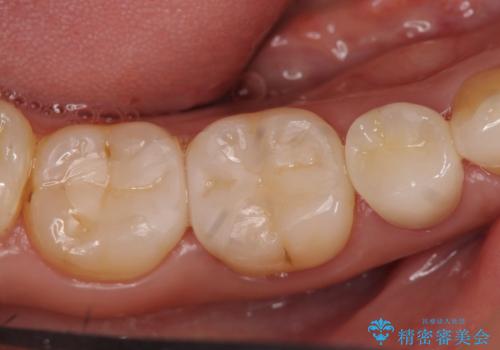

- 右下の奥歯がしみるので診て欲しいといらっしゃった方の症例です。

右下5は虫歯が大きかったため、虫歯を除去後、オールセラミッククラウンによる補綴を行いました。

右下6、7は虫歯を除去後、セラミックインレーによる修復を行いました。